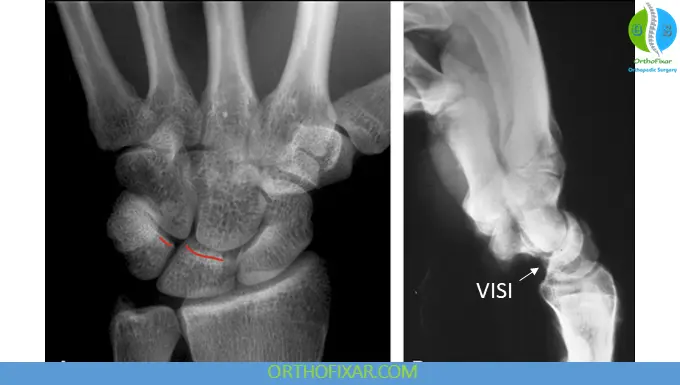

Standard PA View

- Often normal

- May show subtle disruption of the proximal carpal arc

Radial Deviation View

- Triquetrum appears dorsiflexed

- Scapholunate complex appears palmar flexed

Lateral View

- May demonstrate VISI (Volar Intercalated Segment Instability) pattern

Understanding VISI Deformity

VISI: Volar flexion of lunate due to LT instability

In LT dissociation, the lunate follows the scaphoid into volar flexion, producing a VISI deformity—opposite to the DISI pattern seen in scapholunate injuries.